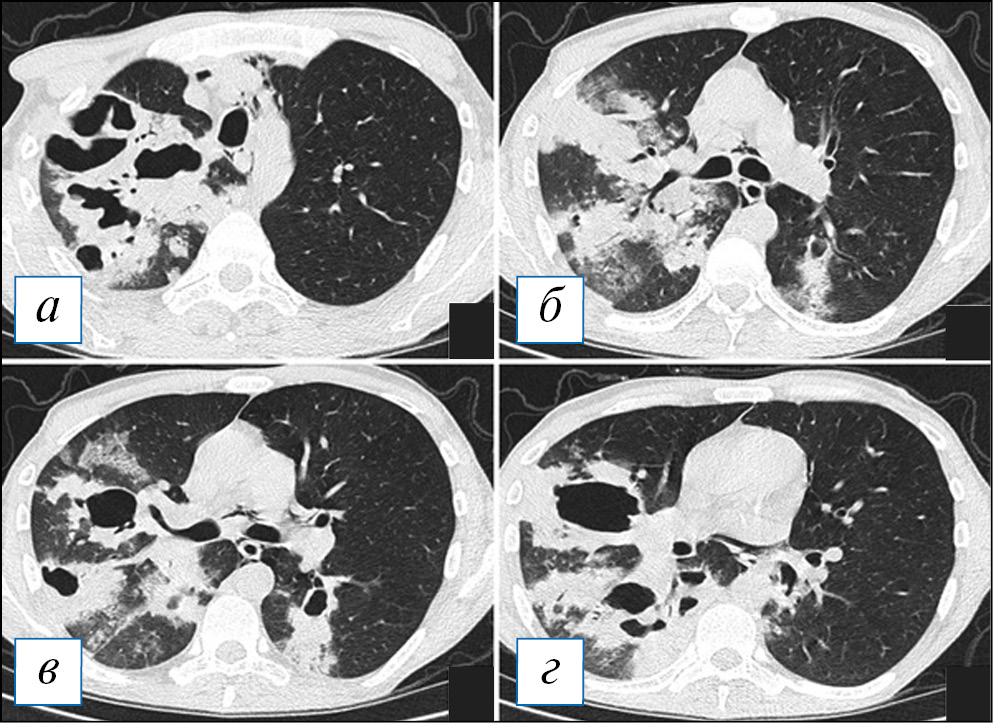

Септическая эмболия по данным КТ наиболее часто представлена округлыми очагами различной плотности и размера (от милиарных до крупных, 12–15 мм), которые располагаются с двух сторон, преимущественно в периферических зонах легких или перибронховаскулярно, где и происходит обтурация сосудов малого калибра эмболами. Очаги гематогенного типа (не имеют четкой связи со структурами интерстиция, часть очагов можно наблюдать вдоль висцеральной плевры) [27] (рис. 4). Поражение одного легкого практически не наблюдается [43].

Рис. 4. Компьютерная томография органов грудной клетки в аксиальной проекции (а, б). Септическая эмболия легких у пациентки с инфекционным эндокардитом трикуспидального клапана. В картине поражения легких преобладают как уже сформированные округлые полости, так и формирующиеся из субплевральных уплотнений с четкими контурами (стрелки). [Изображения из архива авторов]. / Fig. 4. Chest CT, axial projection (а, б). Septic embolism in a patient with infectious endocarditis of the tricuspid valve. In the picture of the lung damage, one can see predominance of both completely formed rounded cavities and those formed from subpleural opacities with clear contours (arrows). [Images from the authors’ archive].

В то же время наряду с очагами в легких появляются участки инфильтрации с четкими контурами (по типу консолидации), различных размеров, также преимущественно в периферической зоне. В ряде случаев эти участки могут быть окружены зоной «матового стекла» (симптом «венца», «halo» sign) или по типу «обратного венца» («reversed halo» sign) — зоны «матового стекла», окруженной по периферии полоской консолидацией различной толщины [50]. Данные КТ-симптомы главным образом представляют сформированные участки инфарктов легкого в сочетании с воспалительной инфильтрацией (рис. 5).

Рис. 5. Компьютерная томография органов грудной клетки в аксиальной проекции (а–г). Септическая эмболия легких у пациента с инфекционным эндокардитом. В обоих легких с преобладанием в периферических отделах определяются очаги, небольшие полости, а также уплотнения смешанного типа (консолидация в сочетании с «матовым стеклом»), отображающие участки инфарктов. Малый плевральный выпот слева. [Изображения из архива авторов]. / Fig. 5. Chest CT, axial projection (а–г). Septic embolism in a patient with infectious endocarditis. In both lungs, with a predominance in the peripheral parts, foci, small cavities, as well as opacities of a mixed type (consolidation in combination with «ground glass») are determined, reflecting the areas of infarcts. Minor pleural effusion on the left. [Images from the authors’ archive].

По ходу течения инфекционного процесса начинается преобразование очагов и инфильтратов с образованием в них участков распада, гнойные массы из очагов и полостей дренируются через бронхи и бронхиолы, оставляя на своем месте тонкостенные полости. Полости распада при септической эмболии чаще имеют правильную округлую, как бы штампованную форму и преимущественное периферическое расположение. В полостях можно наблюдать перегородки, наличие небольшого количества жидкости [43]. Важный дифференциальный признак септической эмболии — быстрое течение с отрицательной динамикой и преобразование очагов и уплотнений в характерные полости.